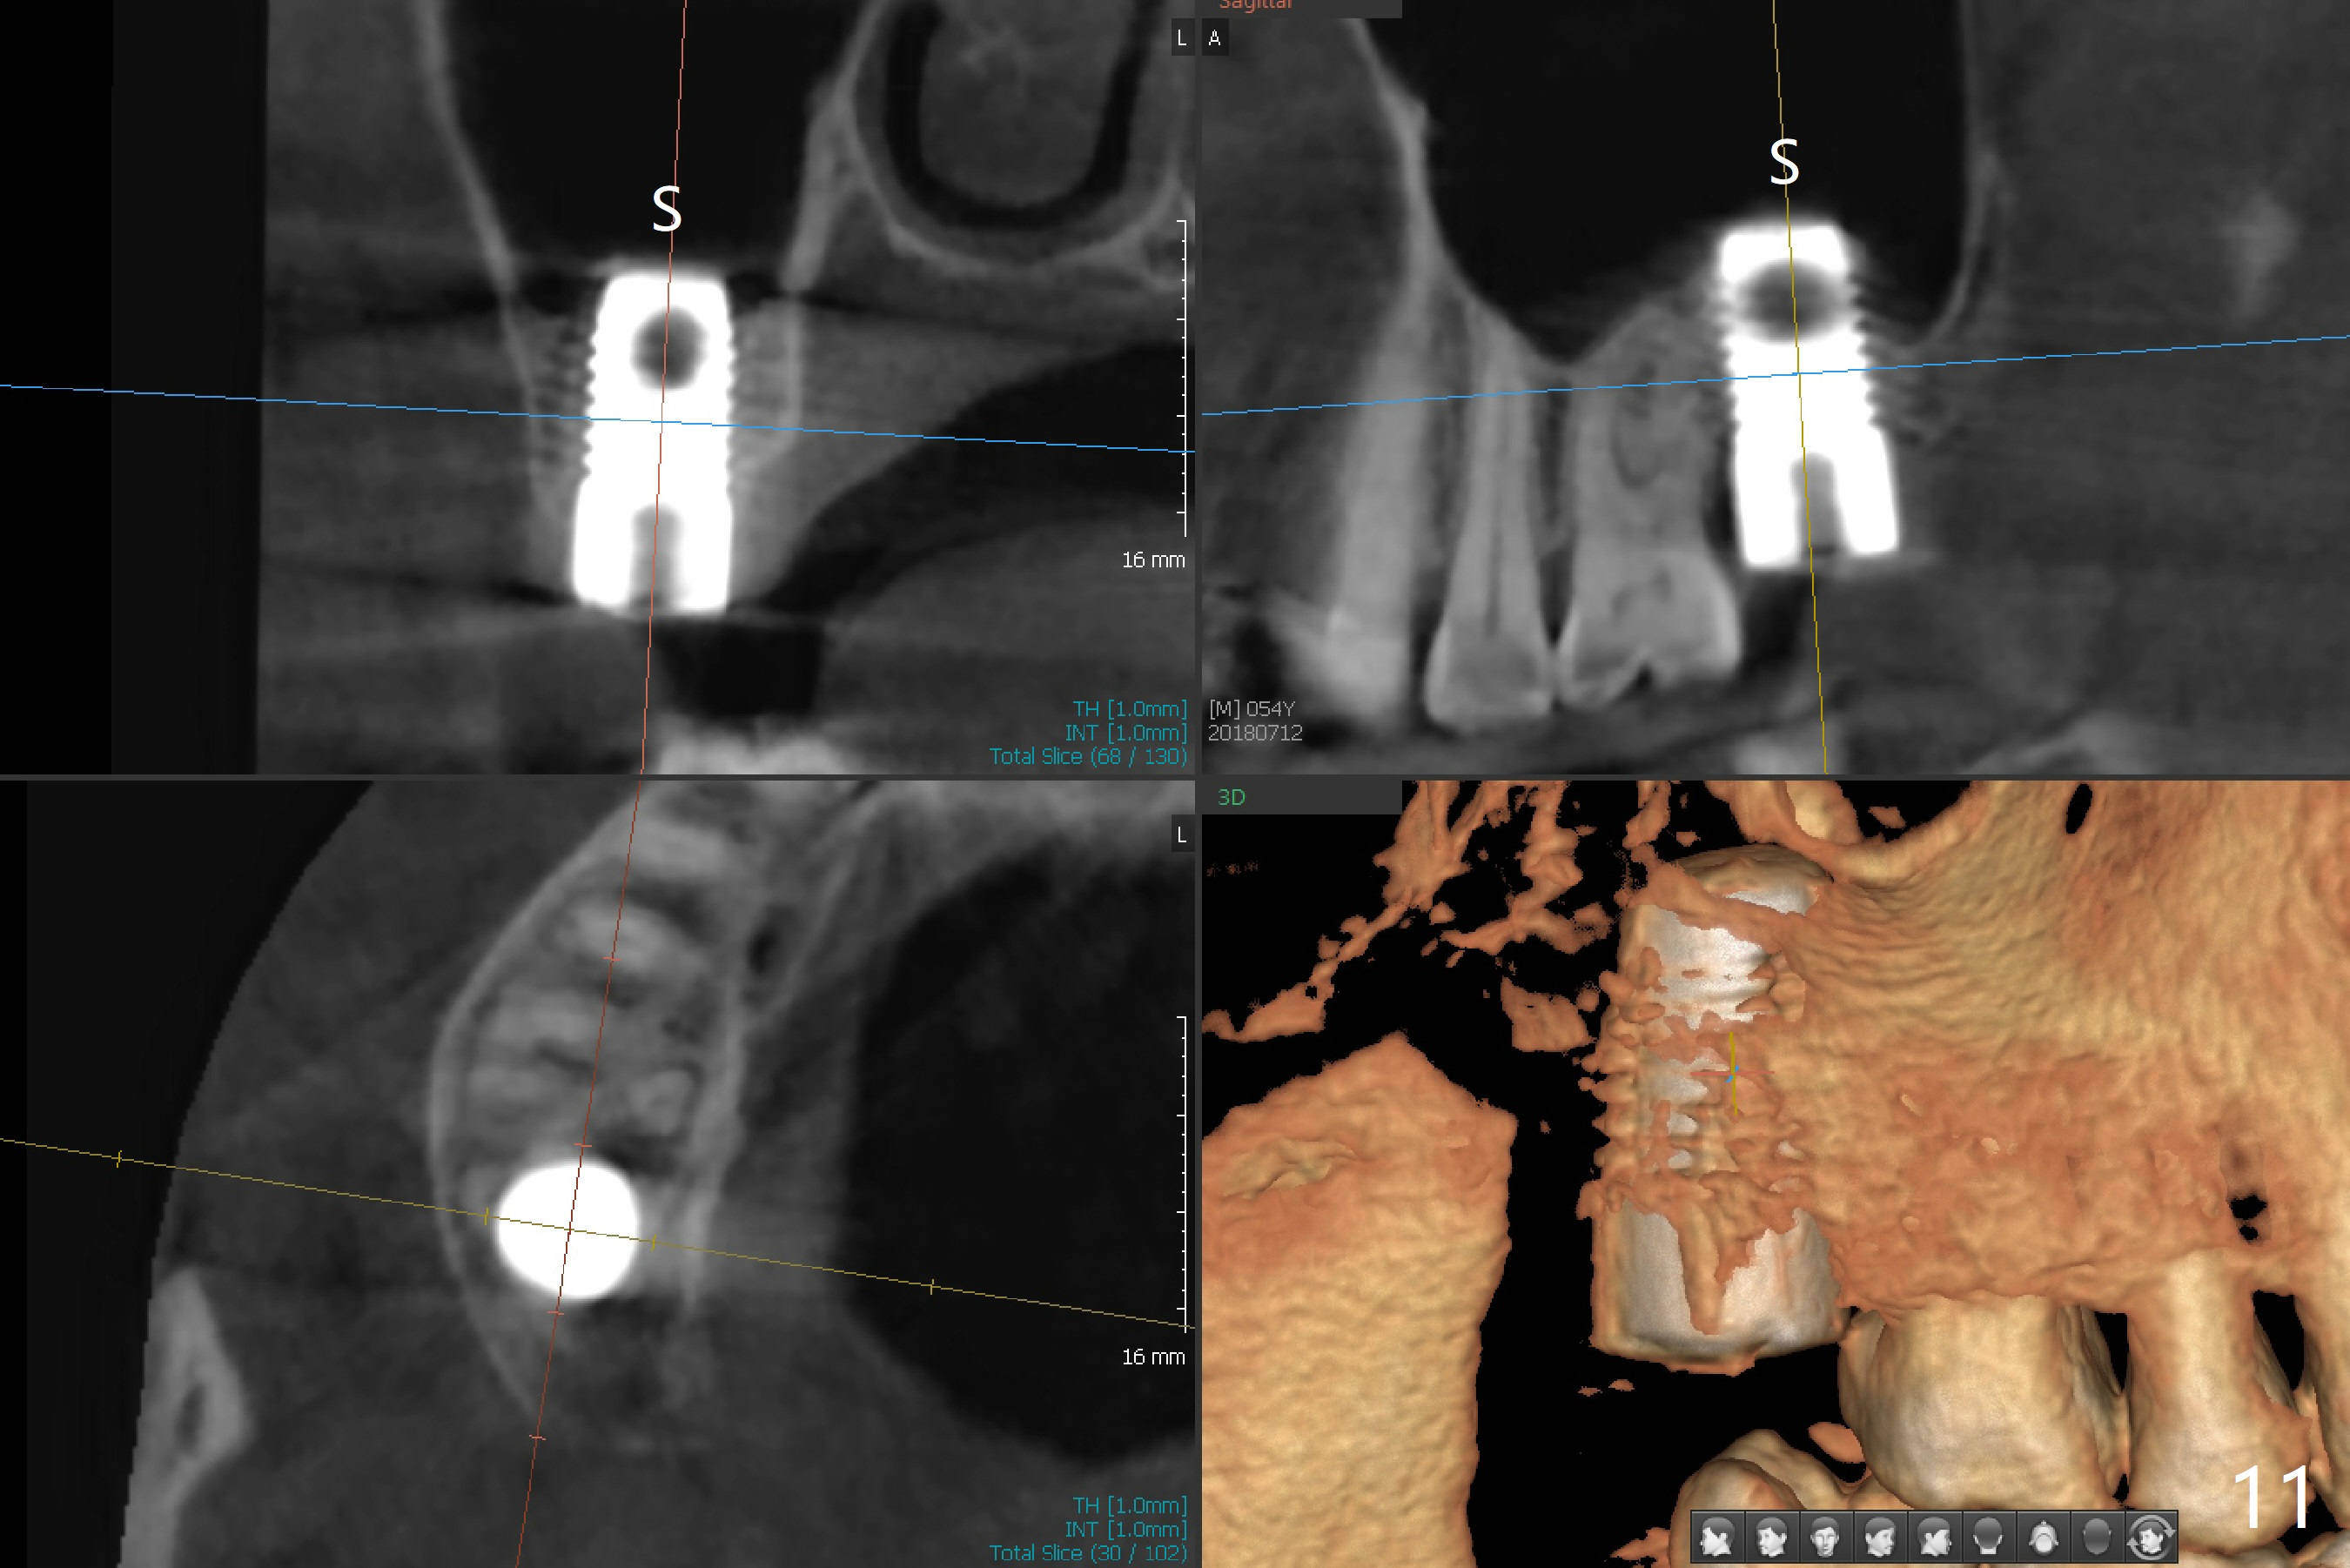

Preop exam shows that the tooth #2 has split into the buccal (Fig.1 B) and palatal (P) halves. When the tooth is extracted (Fig.2), there is a large piece of granulation tissue between these halves. The socket is large with sinus floor having pointed perforation. The latter is enlarged with rounded tapered Tatum osteotomy 2-4 mm, followed by tapered and then rounded taps. A 6.8x14 mm rounded tap has barely enough stability (Fig.3). Following placement of 2 PRF plug and 2 PRF membranes and allograft/Osteogen, a 8x17 mm cylindrical implant is placed with 60 Ncm (implant machine reading), however the implant is unstable (Fig.4). More graft is placed around the implant. With placement of 6x3 mm abutment, an immediate provisional is fabricated to close the socket. There is nasal discharge for a few days postop. PAs taken nearly 6 months postop show no bone loss (Fig.5,6). The definitive crown is cemented with access hole; there is no residual cement (Fig.7 (9 months postop)). The crown is loose 1 month post cementation (last March, Fig.8 with periimplant space (*)). The unipost was not cemented due to gag reflex. He refuses treatment immediately because of the allergy season. When he returns, spray a topical to his throat. Following crown removal, implant is found to have mobility. Panoramic X-ray (Fig.9) and CT (Fig.10,11) show fibrointegration (space) and implant intrusion into the sinus (S) without bone formation. After implant removal, the sinus floor and membrane are found to have been perforated. Osteogen plug is placed, followed by Vanilla/Osteogen (Fig.12 *) and Osteogen plug. It appears that an immediate implant is contraindicated when there is severe infection (Fig.2) with sinus floor perforation. In this case, the bone density at the upper 2nd molar is low (Fig.10 distopalatal view of 3-D image). Bone expansion and condensation is needed for implantation. Progressive loading is also necessity prior to impression.